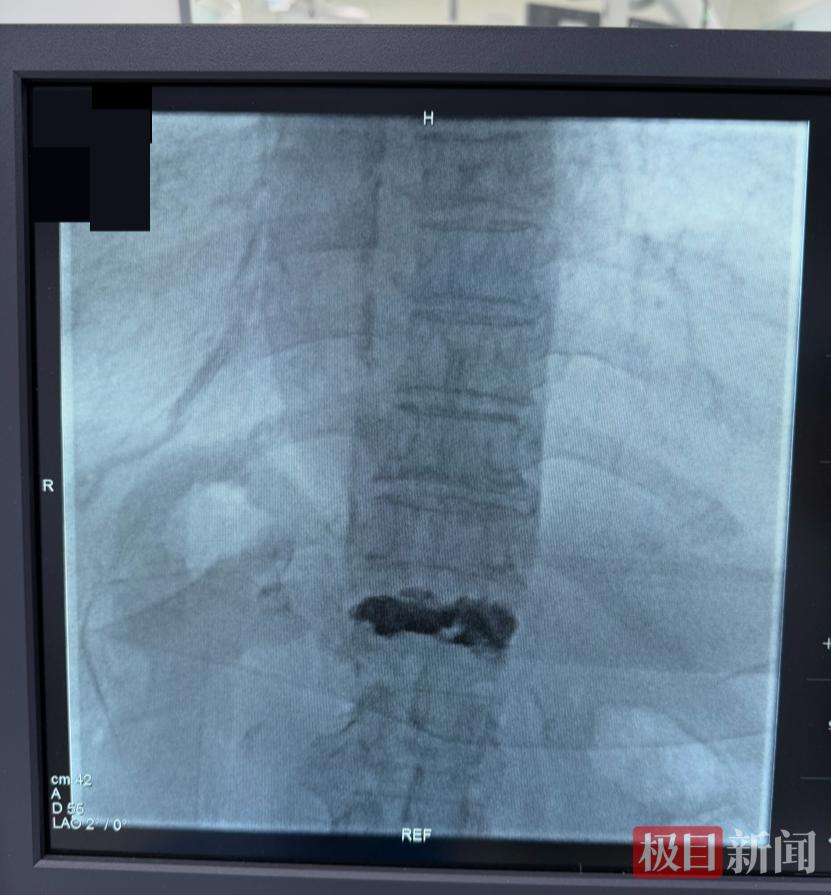

术中,为了在X光引导下将骨水泥精准注入骨折椎体,同时最大限度缩短手术时间、降低风险,主刀医生吴群主任与助手穿上重达40斤的铅衣,在厚重的防护下连续奋战,通过仅黄豆大小的切口,完成了椎体“铸骨”成形手术。整个过程平稳迅速,最大限度减少了手术对老人身体的影响。

正侧位可见压缩的椎体被骨水泥填充完整